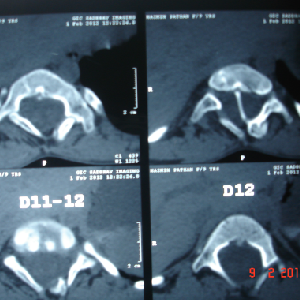

Double cord syndrome – DIASTOMATOMYELIA – is a very rare entity, wherein patient

is having congenital deformity of spine with separation of the spinal cord into

two halves by a bony or fibrous septum It is a great challenge to operate these

pts as , if something goes wrong, pt would become paraplegic for her life time.

Perticularly, in this case, as pt was only 9 years old and having congenital deformity

of the vertebrae, it was corrected simultaneously at Sola civil hospital - ahmedabad.